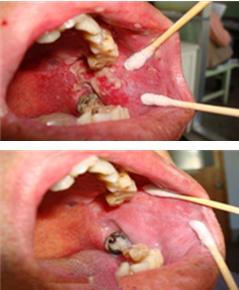

具有“黄、红、凹、痛”的临床特征,即溃疡表面覆盖黄色假膜、周围有红晕带、中央凹陷、疼痛明显......[详情]

1、产生热能效应,改善血液循环,促进黏膜修复

2、清除局部炎症细胞,加速病损愈合<1ML

3、在表面坏死组织产生汽化、凝固,达到消炎止痛作用